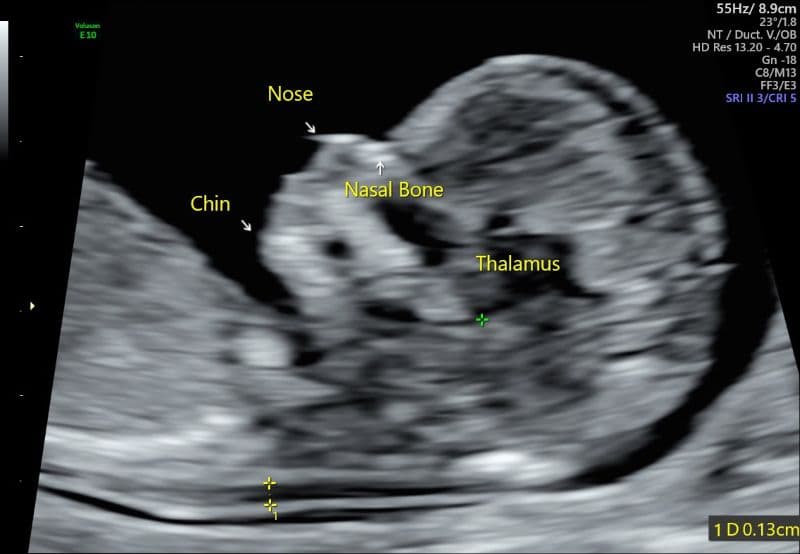

Đánh giá chiều dài xương mũi của thai nhi 24 tuần cần được đối chiếu với các bảng bách phân vị tiêu chuẩn. Theo một nghiên cứu quy mô trên quần thể thai nhi châu Á (cụ thể là ở Ấn Độ), sự phát triển của xương mũi tăng dần theo tuổi thai. Cụ thể, theo PubMed Central, tại mốc thời gian tuần thứ 24:

- Chỉ số bách phân vị thứ 5 (ngưỡng giới hạn dưới): 4,68 mm.

- Chỉ số bách phân vị thứ 50 (mức trung vị): 6,40 mm.

- Chỉ số bách phân vị thứ 75: 7,00 mm.

Như vậy, khi giải đáp thắc mắc thai 24 tuần chiều dài xương mũi bao nhiêu là bình thường, các chuyên gia y tế sẽ dựa vào các mốc trên để làm chuẩn. Với kết quả siêu âm chiều dài xương mũi thai nhi 24 tuần 7mm, chỉ số này nằm đúng ở bách phân vị thứ 75, cao hơn mức trung vị của thai nhi bình thường. Do đó, kết quả này là một tín hiệu rất tốt, bởi “nếu chiều dài xương mũi không thấp hơn mức tiêu chuẩn, đó là một dấu hiệu cho thấy thai nhi phát triển khỏe mạnh”.

Chỉ số có thể dao động nhẹ tùy thuộc vào tư thế em bé lúc đo lường, ví dụ như “mặt hướng về đầu dò siêu âm, đầu và cổ tạo thành một đường thẳng, da phía trước xương mũi vuông góc với sóng siêu âm”.